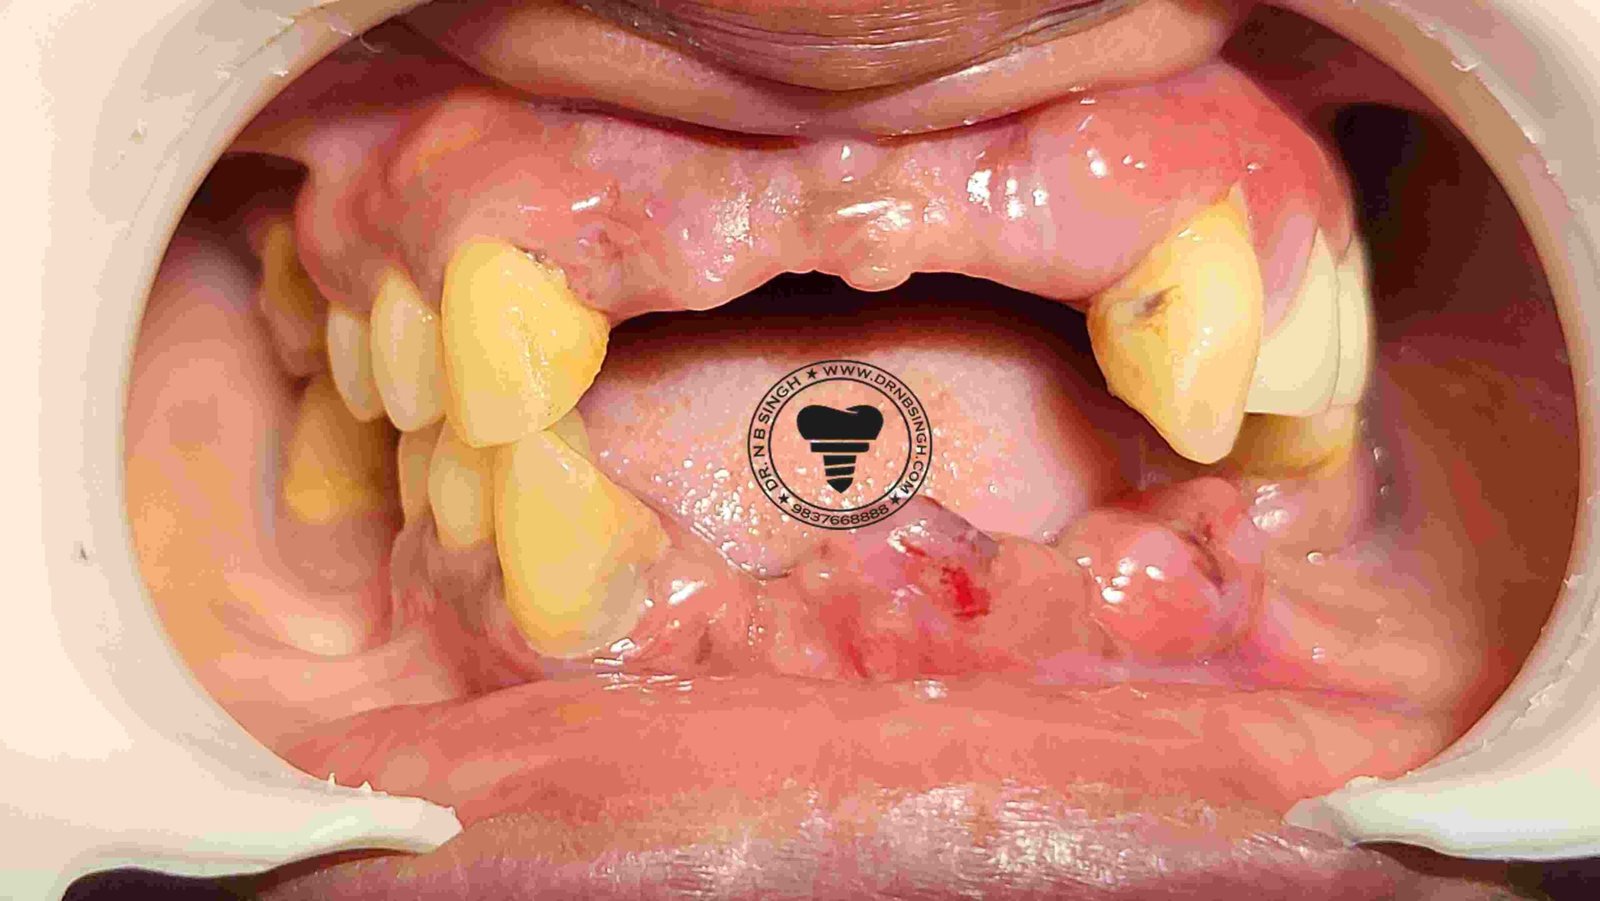

1002 Basal Full Mouth Implants Case Rubeena 2

1002 basal implant full mouth case rub 4